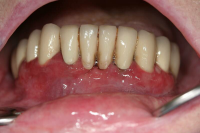

Förekomst av gingivala hyperplasier med djupa tandköttsfickor och svåra hygienförhållanden som följd.

En volymökning av mjukvävnaden kring tänderna som är associerad med intag av läkemedel tillhörande grupperna antiepileptika, immunosuppressiva läkemedel och kalciumblockerare.

Inflammation är den utlösande faktorn som driver tillväxten av mjukvävnaden därför är plackkontroll av största vikt.